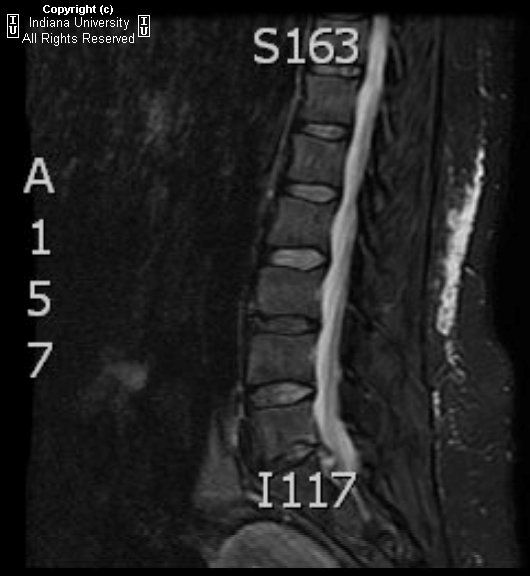

Lumbar spinal MRI of the patient. A intradural mass with high signal Vertebral Disc Enhancement Spondylodiscitis can also mimic modic type 1 degenerative changes, which show low t1 signal, high t2 signal and may have enhancement at the endplates. mri is the standard imaging modality for detecting disc pathology due to its advantage of lack of radiation,. mri is most sensitive in assessing degenerative disc changes (signal change, disc height reduction, herniation,. . Vertebral Disc Enhancement.